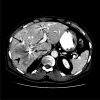

Background: Preoperative portal vein embolization (PVE) is increasingly used as a preparation for major hepatectomy in patients with inadequate liver remnant volume or function. However, whether segment 4 (S4) portal veins should be embolized is controversial. The effect of S4 PVE on the volume gain of segments 2 and 3 (S2+3) was examined.

Methods: Among 73 patients with uninjured liver who underwent right portal vein embolization (RPVE, n = 15) or RPVE extended to S4 portal veins (RPVE+4, n = 58), volume changes in S2+3 and S4 after embolization were compared. Clinical outcomes and PVE complications were assessed.

Results: After a median of 27 days, the S2+3 volume increased significantly after both RPVE and RPVE+4, but the absolute increase was significantly higher for RPVE+4 (median, 106 mL vs 141 mL; P = .044), as was the hypertrophy rate (median, 26% vs 54%; P = .021). There was no significant difference between RPVE and RPVE+4 in the absolute S4 volume increase (52 mL for RPVE vs 55 mL for RPVE+4; P = .61) or the hypertrophy rate of S4 (30% for RPVE vs 26% for RPVE+4; P = .45). Complications of PVE occurred in 1 patient (7%) after RPVE and 6 (10%) after RPVE+4 (P > .99). No PVE complication precluded subsequent resection. Curative hepatectomy was performed in 13 patients (87%) after RPVE and 40 (69%) after RPVE+4 (P = .21).

Conclusions: RPVE+4 significantly improves S2+3 hypertrophy compared with RPVE alone. Extending RPVE to S4 does not increase PVE-associated complications.